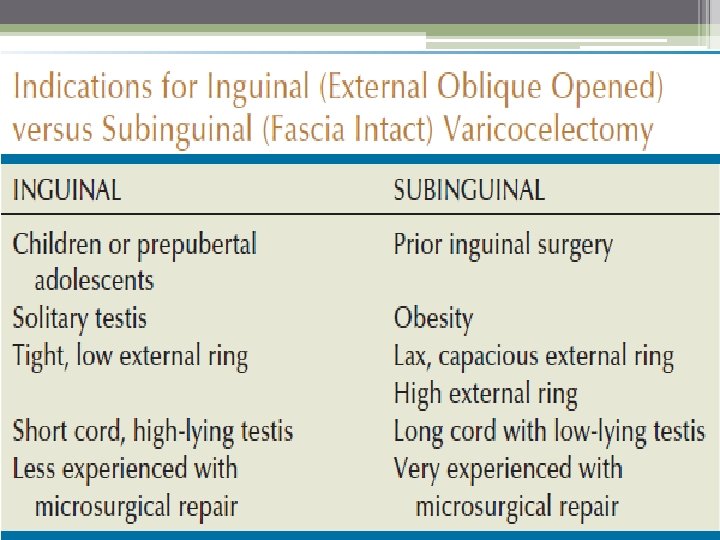

The Inguinal Approach can be used in almost any patient It allows for mobilization of the cord, identification of any large veins within the cremasteric muscle. identification of veins perforating the posterior inguinal canal that might be contributing to the varicocele. Conventional inguinal operations are associated with an incidence of postoperative hydrocele formation varying from 3% to 15%.

Subinguinal Approach The incision is made just below the level of the external inguinal ring The advantage of this technique is that it requires a small incision with no abdominal muscle or fascia cut. At the subinguinal level, however, significantly more veins are encountered. identification and preservation of testicular artey more difficult it is best to use in men with a history of any prior inguinal surgery.